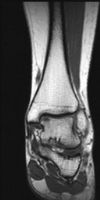

MRI Ankle - T1W - Coronal -Osteochondral defect-superior medial aspect of the talar dome 01